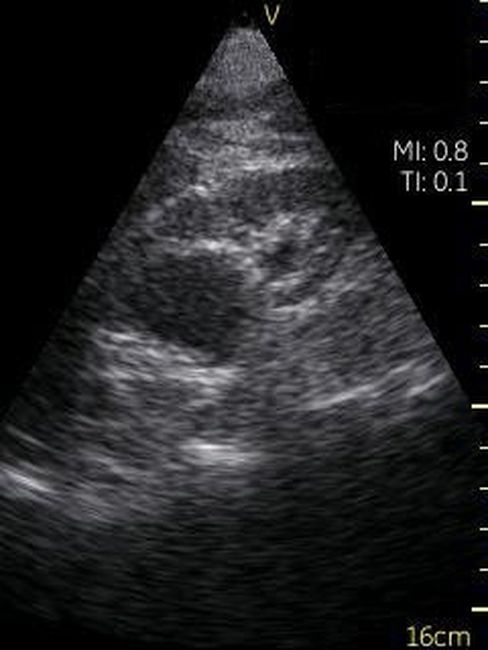

GE VSCAN – это УЗИ аппарат, реализованный в ультракомпактном корпусе, позволяющий делать черно-белые изображения тканей и органов реального времени. Ключевым отличием данного прибора от других моделей GE является его карманный размер, он чуть больше обычного смартфона. Идеальное средство для бригад скорой помощи, врача, принимающего пациента на дому, экстренной диагностики в полевых условиях.

Невозможно было представить раньше, что УЗИ аппарат может помещаться на ладони руки человека. Теперь это реальность, воплощенная в корпусе и технологической начинке GE VSCAN. Инженеры заложили возможность получения дополнительной визуализации кровотока с цветной кодировкой в режиме реального времени для полноценной постановки диагноза на месте.

Визуализация Vscan:

· Черно-белый режим для визуализации анатомических структур в реальном времени.

· Наложение кровотока с цветовой кодировкой в реальном времени.

· Поле зрения в черно-белом режиме: до 75 градусов с максимальной глубиной 25 см.

· Сектор цветного режима показывает кровоток с углом обзора 30 градусов

· Широкополосный фазированный датчик с частотой от 1,7 до 3,8 МГц.